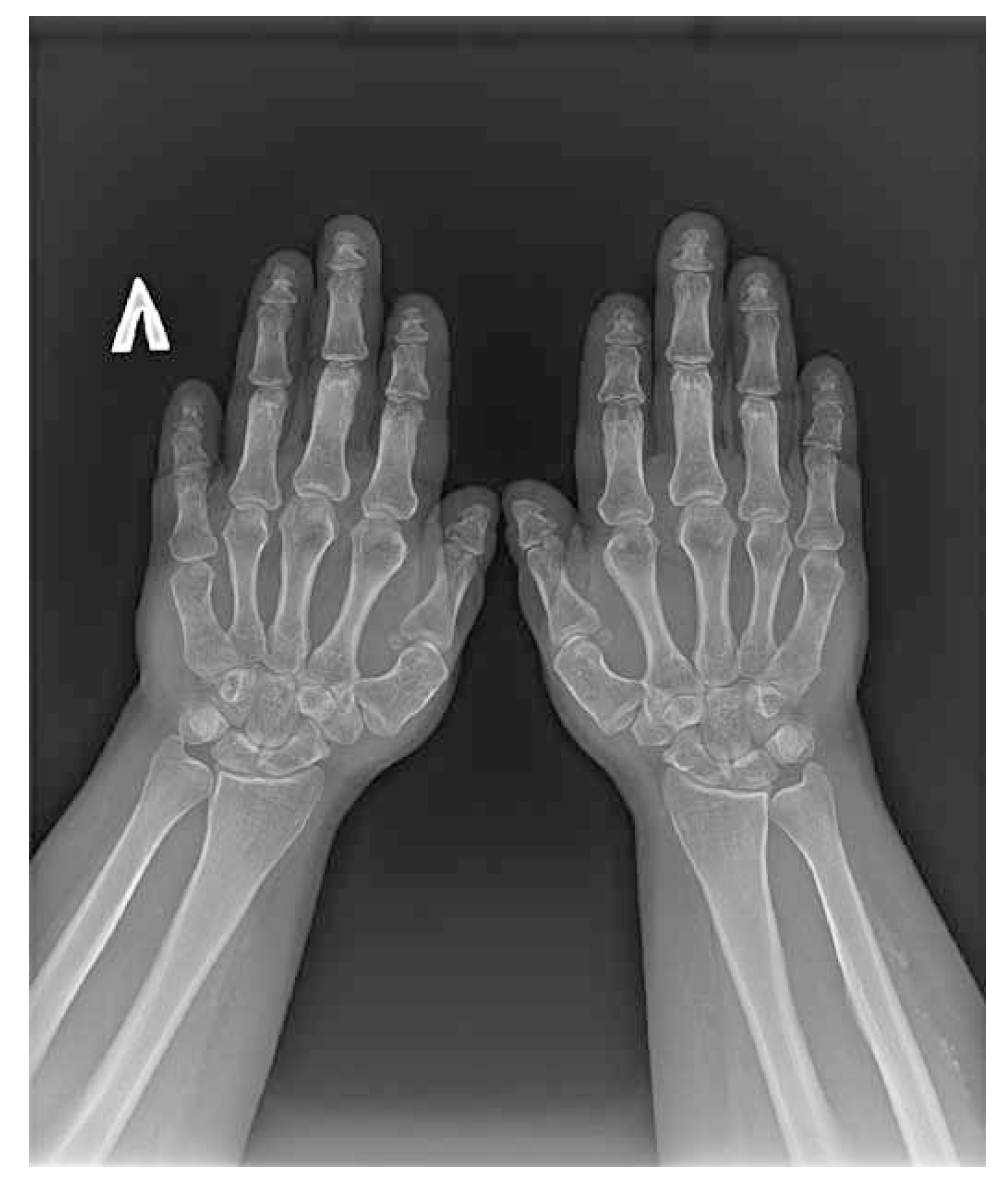

9. Fig. 1. Brahidactyly: pronounced shortening of the fifth metacarpal bone to the left. | |

10. Fig. 2. Brahidactyly: shortening of the IV metatarsal to the left. | |